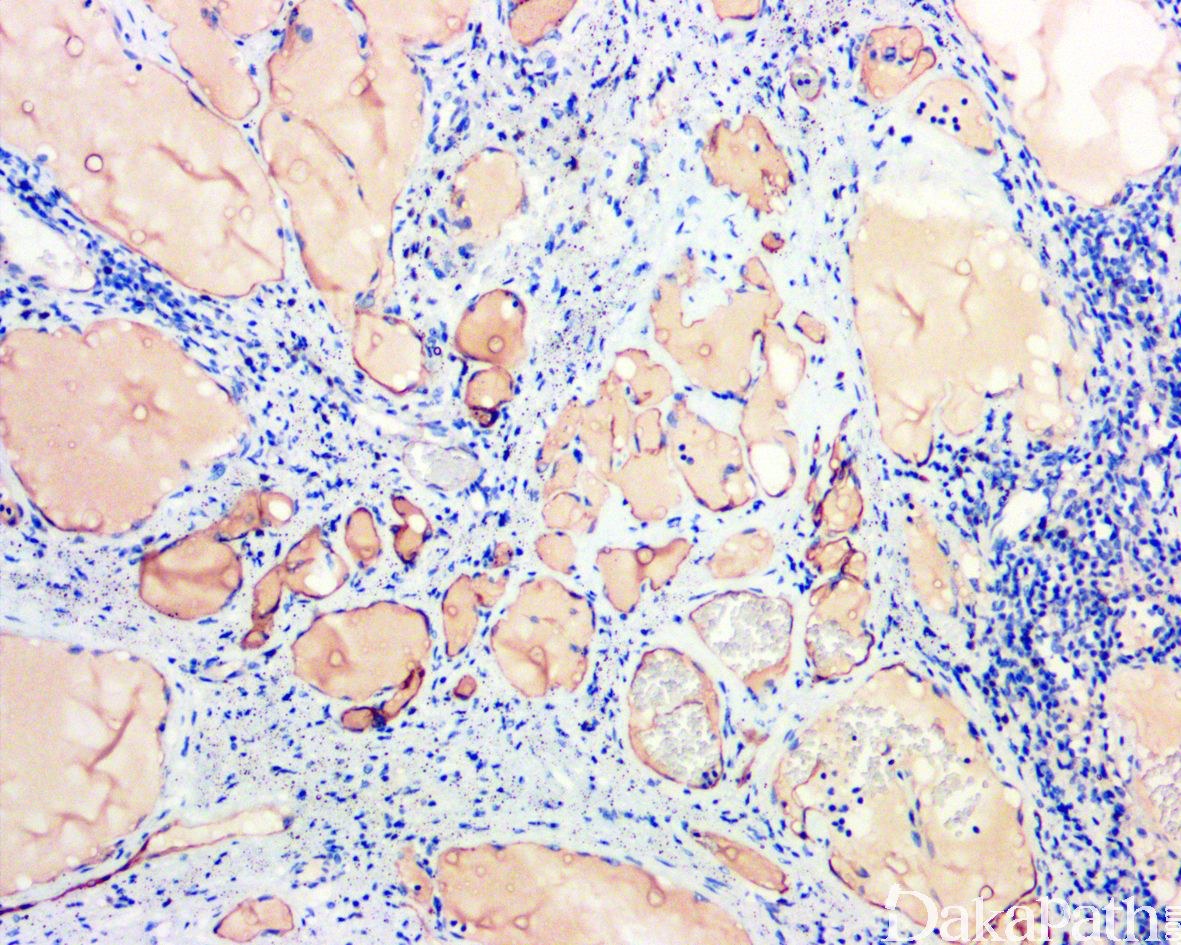

.镜下由大小不等的腔隙组成,腔内壁衬以单层的扁平内皮细胞,腔内充满蛋白性液体,常可见淋巴细胞,有时可见红细胞;

在大的腔隙周围常可见不完整的平滑肌。

淋巴管内皮 D2-40. VEGFR-3 及 LyVE-1 常呈阳性,不同程度表达血管标记 CD31. CD34 及 FVIIIRAg。